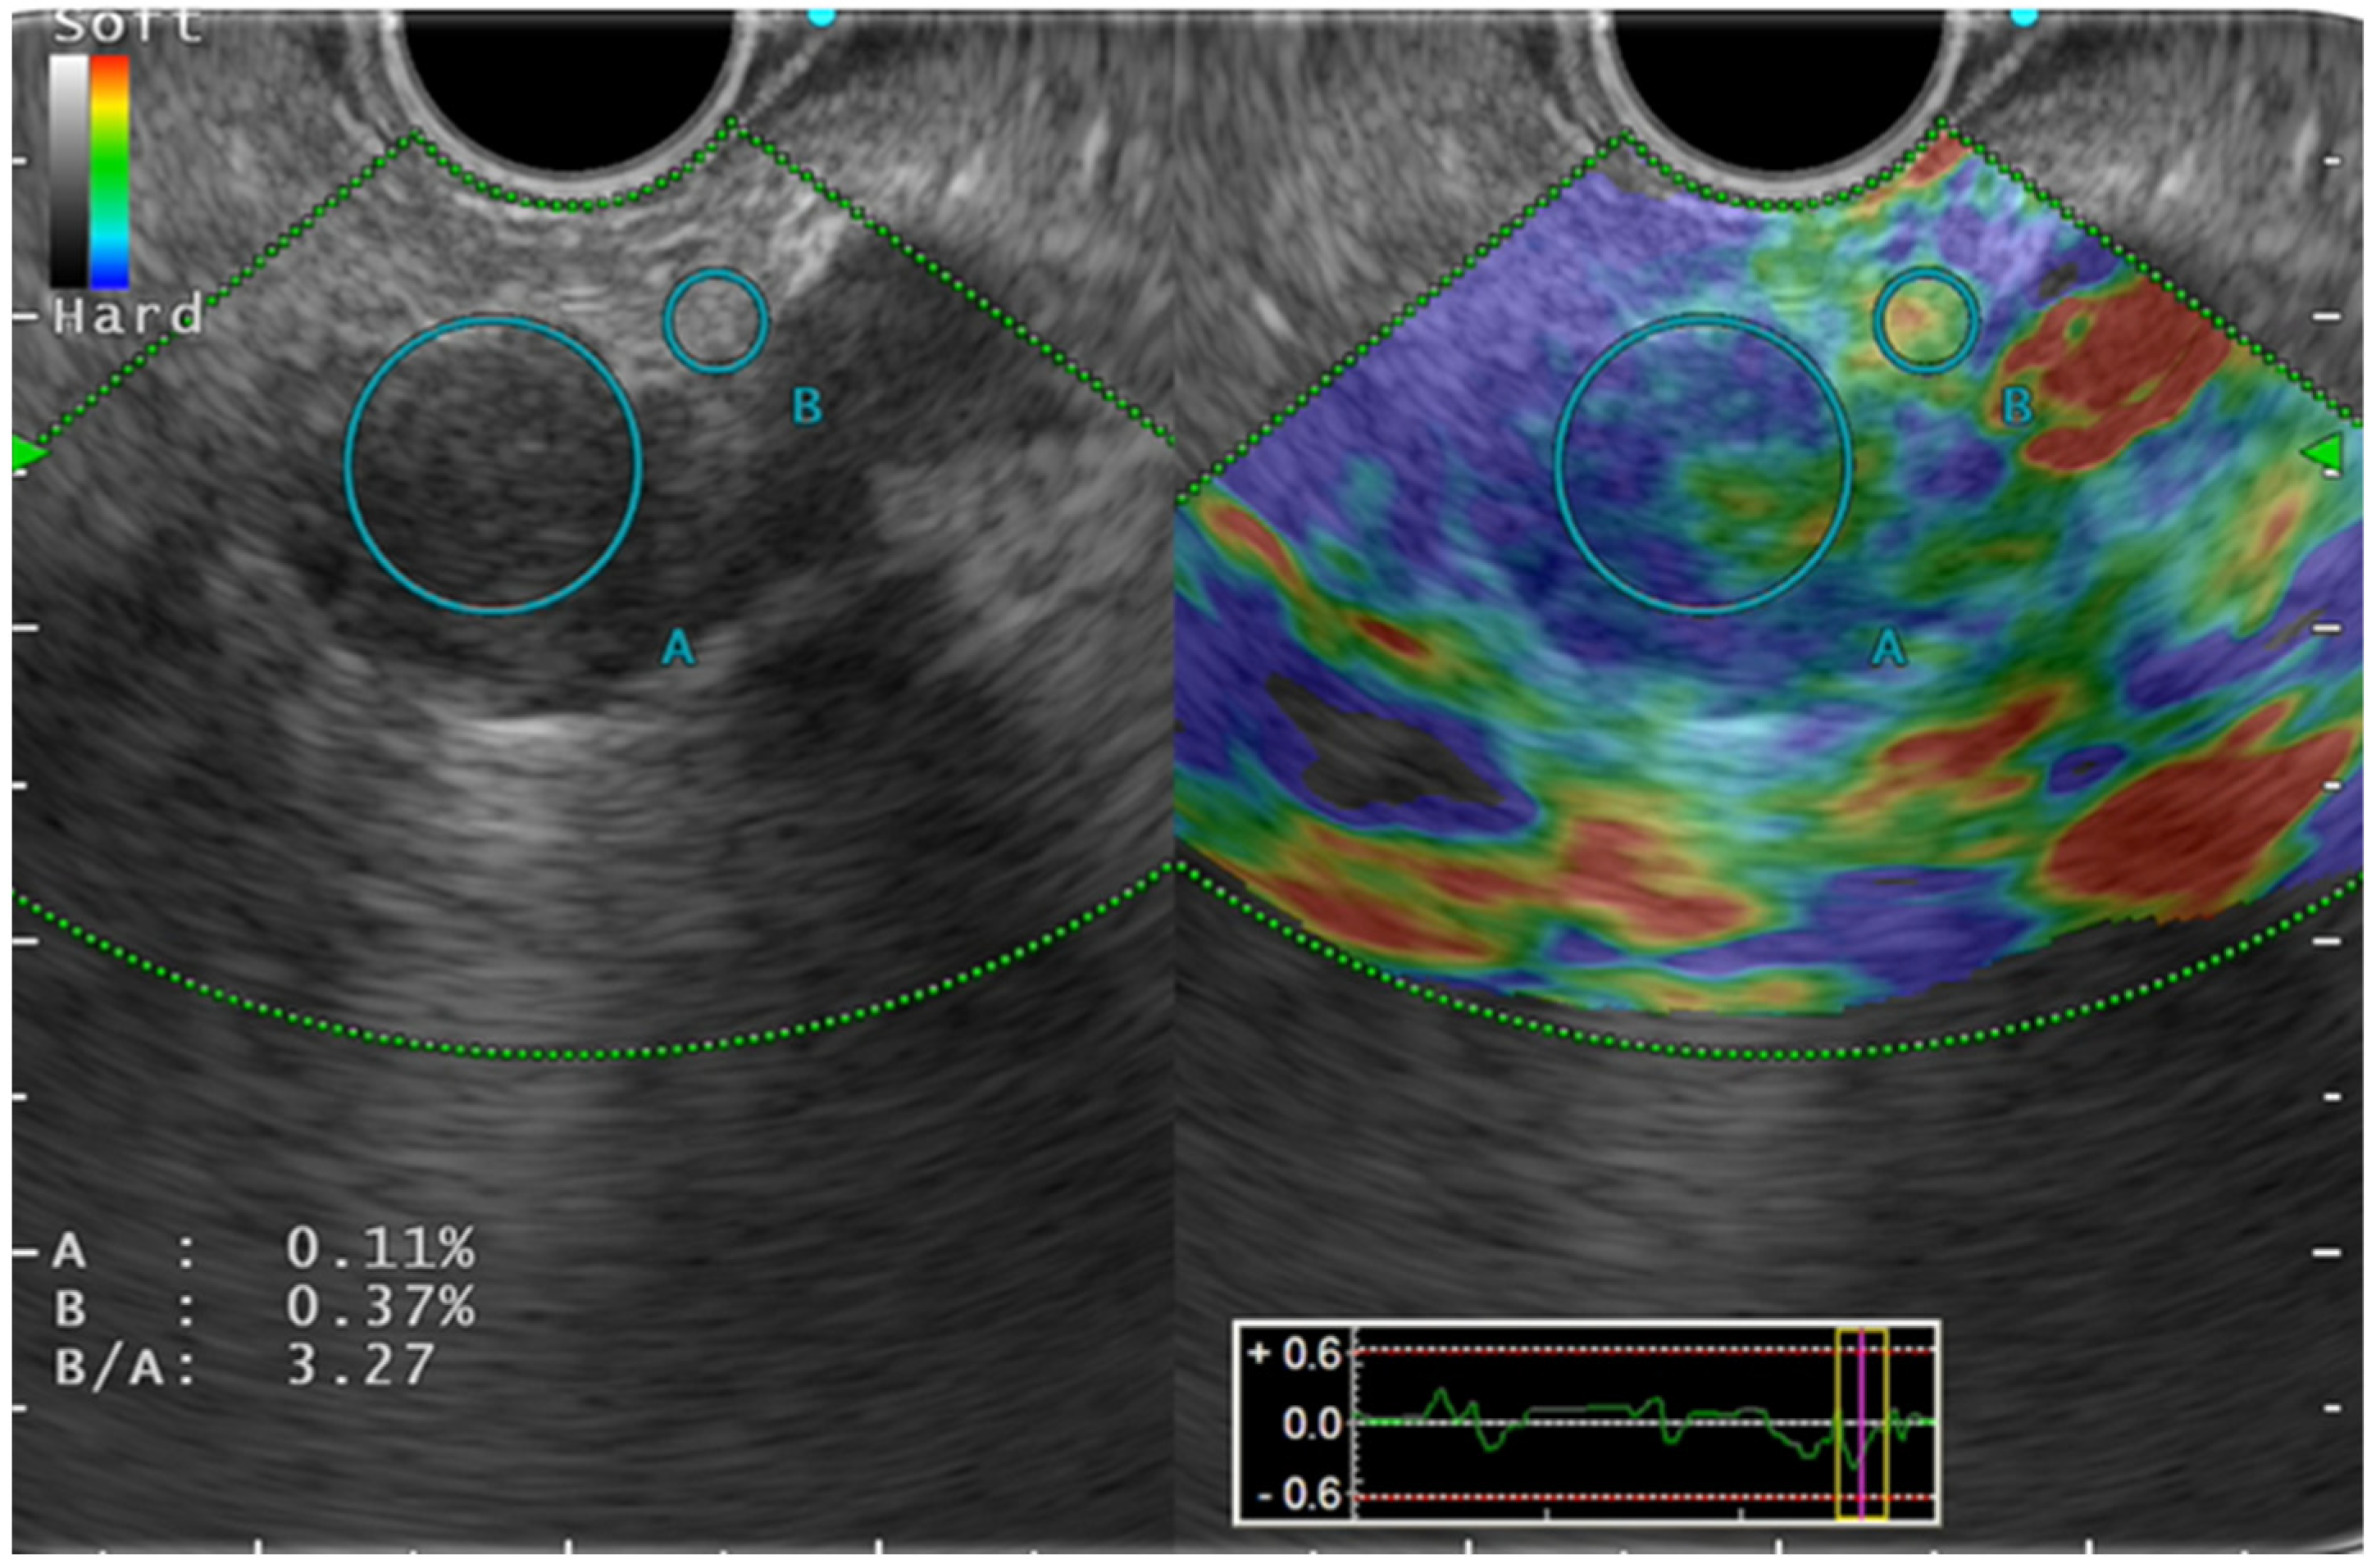

Color pattern diagnosis is the qualitative evaluation method used for SE (Figure 1). Generally speaking, color pattern diagnosis is used for major color tones of tumors (blue, hard; red, soft), and for heterogeneous or homogeneous color tones. Giovannini et al. first reported the elastic score: a color pattern diagnosis. The elastic score, color pattern, and heterogeneity of distribution of the elastography were classified into five types [13]. The quantitative evaluation methods are classified into SR and SH. The former, SR, is the ratio of the target lesion strain to the peripheral tissue strain [14]. The latter, SH, evaluates a grayscale histogram created by converting an elastography image into a gray scale of 256 tones, thereby yielding feature values [15]. The mean value, which is one of the feature values, is reportedly correlated with the degree of pathological pancreatic fibrosis. The SH results, used along with neural network analysis (NN), are particularly valuable for differential diagnosis of pancreatic cancer from pancreatic inflammatory masses [16].

Figure 1.

Strain elastography.